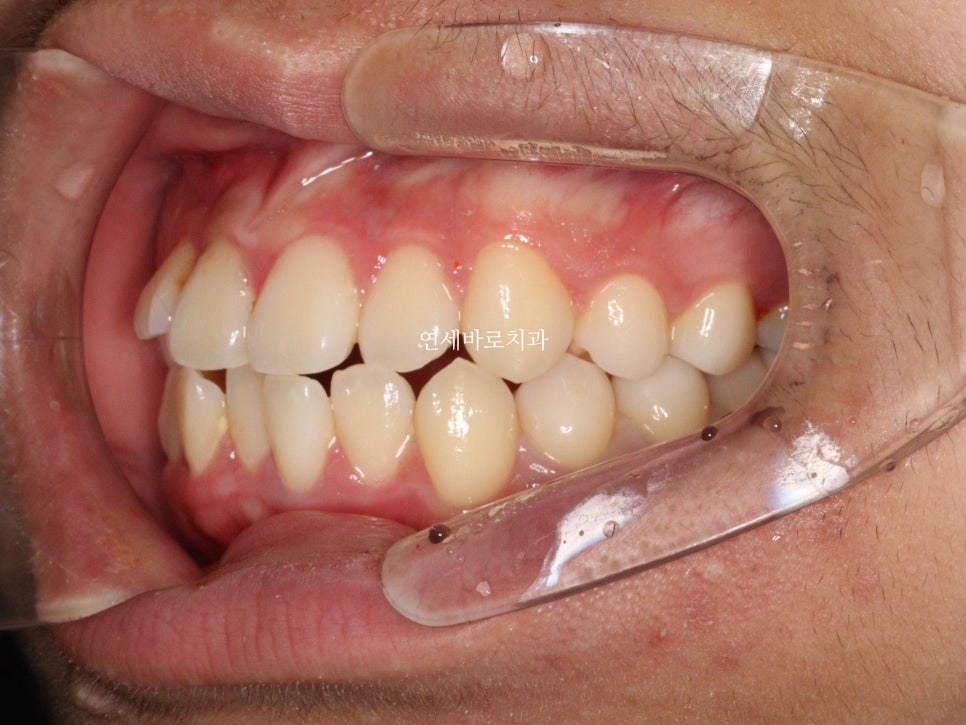

거의 끝나가 아래쪽 장치를 먼저 제거했습니다.

환자가 불편하다고 빨리 끝난 쪽이라도 제거를 먼저하길 원했어요

괜찮아요 먼저 제거해도.

그래서 먼저 제거하고 위쪽을 조금 더 진행했습니다.

그리고 24.6. 교정을 시작한지 약 1년 반정도만에 치료가 마무리 되었습니다.

단점은 좌우 대칭이 아니라 약간의 심미적인 문제가 생기는 것입니다.

그 심미적 문제가 이것입니다.

화면의 왼쪽은 작은 어금니

오른쪽은 송곳니 입니다.

그래서 모양이 다르죠.

이런문제가 있긴 하지만 거의 티가 나진 않습니다.

이렇게 보니 차이가 조금 더 크죠?

이런 문제가 있지만 송곳니 발치는 종종 선택되어 집니다.